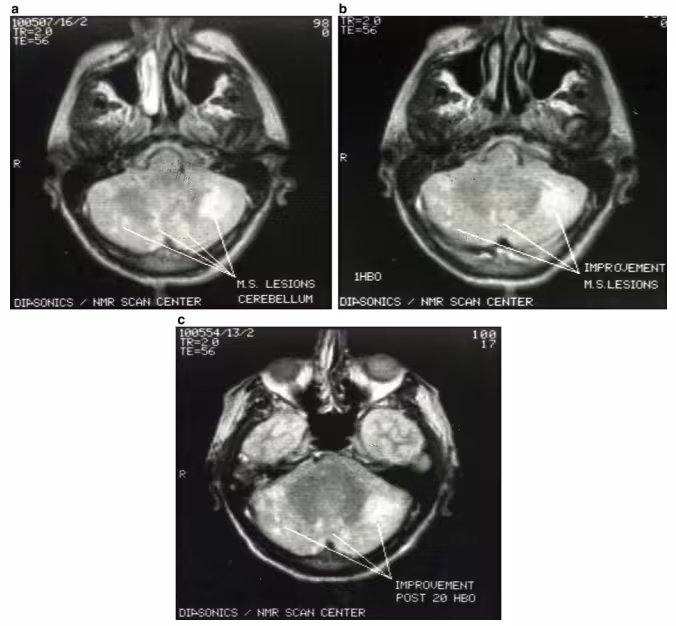

(a) Imagen de resonancia magnética de un paciente de 58 años con esclerosis múltiple y ataxia cerebelosa antes del tratamiento de OHB, mostrando una lesión edematosa. (b) Imagen después de 1 sesión de OHB, mostrando mejoría. (c) Imagen después de 20 sesiones de OHB, mostrando reducción del edema. El paciente mostró una marcada mejoría clínica. (Cortesía del fallecido Dr. Richard A. Neubauer)